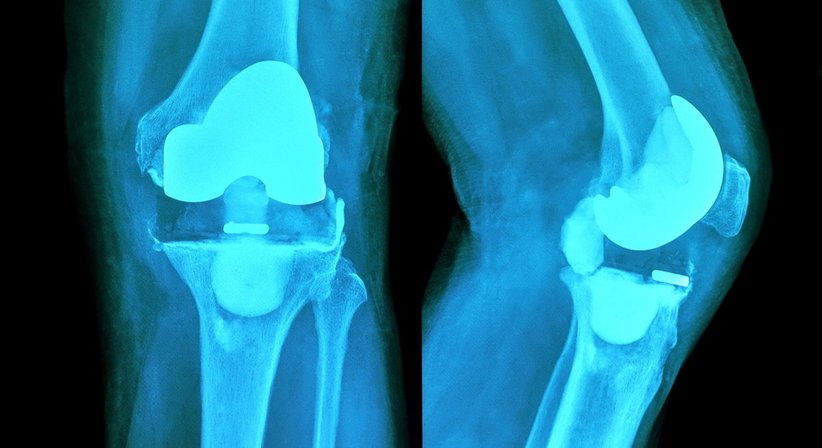

• Knieprothese:

Bei Patienten mit stark fortgeschrittener Kniearthrose, bei welchen mit konservativen Behandlungsverfahren und gelenkerhaltenden Operationsmethoden keine ausreichende Linderung der Beschwerden mehr erreicht werden kann, sollte die Implantation einer Knieprothese in Erwägung gezogen werden.

Eine Knieprothese ahmt die Form und Funktion vom natürlichen Kniegelenk nach und ermöglicht es, Schmerzen und Bewegungseinschränkungen nachhaltig zu beseitigen und die Belastbarkeit vom Knie wiederherzustellen. Unterschieden wird hierbei u. a. zwischen dem vollständigen und dem teilweisen Ersatz vom Kniegelenk - mit einer Teilprothese wird nur ein Teil vom Gelenk ersetzt, das restliche Gelenk bleibt erhalten. Bei Implantation einer Total-Endoprothese wird das gesamte Gelenk durch eine entsprechende Prothese ersetzt. Jeder Knieprothesen-Typ ist in verschiedenen Größen und Varianten verfügbar, was es ermöglicht, die Prothese bestmöglich an die individuellen Bedürfnisse und anatomischen Verhältnisse des Patienten anzupassen.